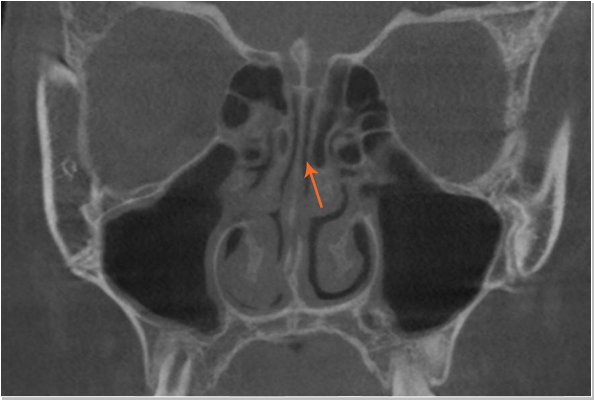

낮은코 내부구조 CT 사진 비중격 만곡증

낮은코 내부구조 CT 사진 커져있는 코덧살(비염)

비중격만곡증 교정술, 고주파 비염수술로 코의 기능을 회복시킴

절골술 및 비중격만곡증 교정술로 휘어진 코 교정